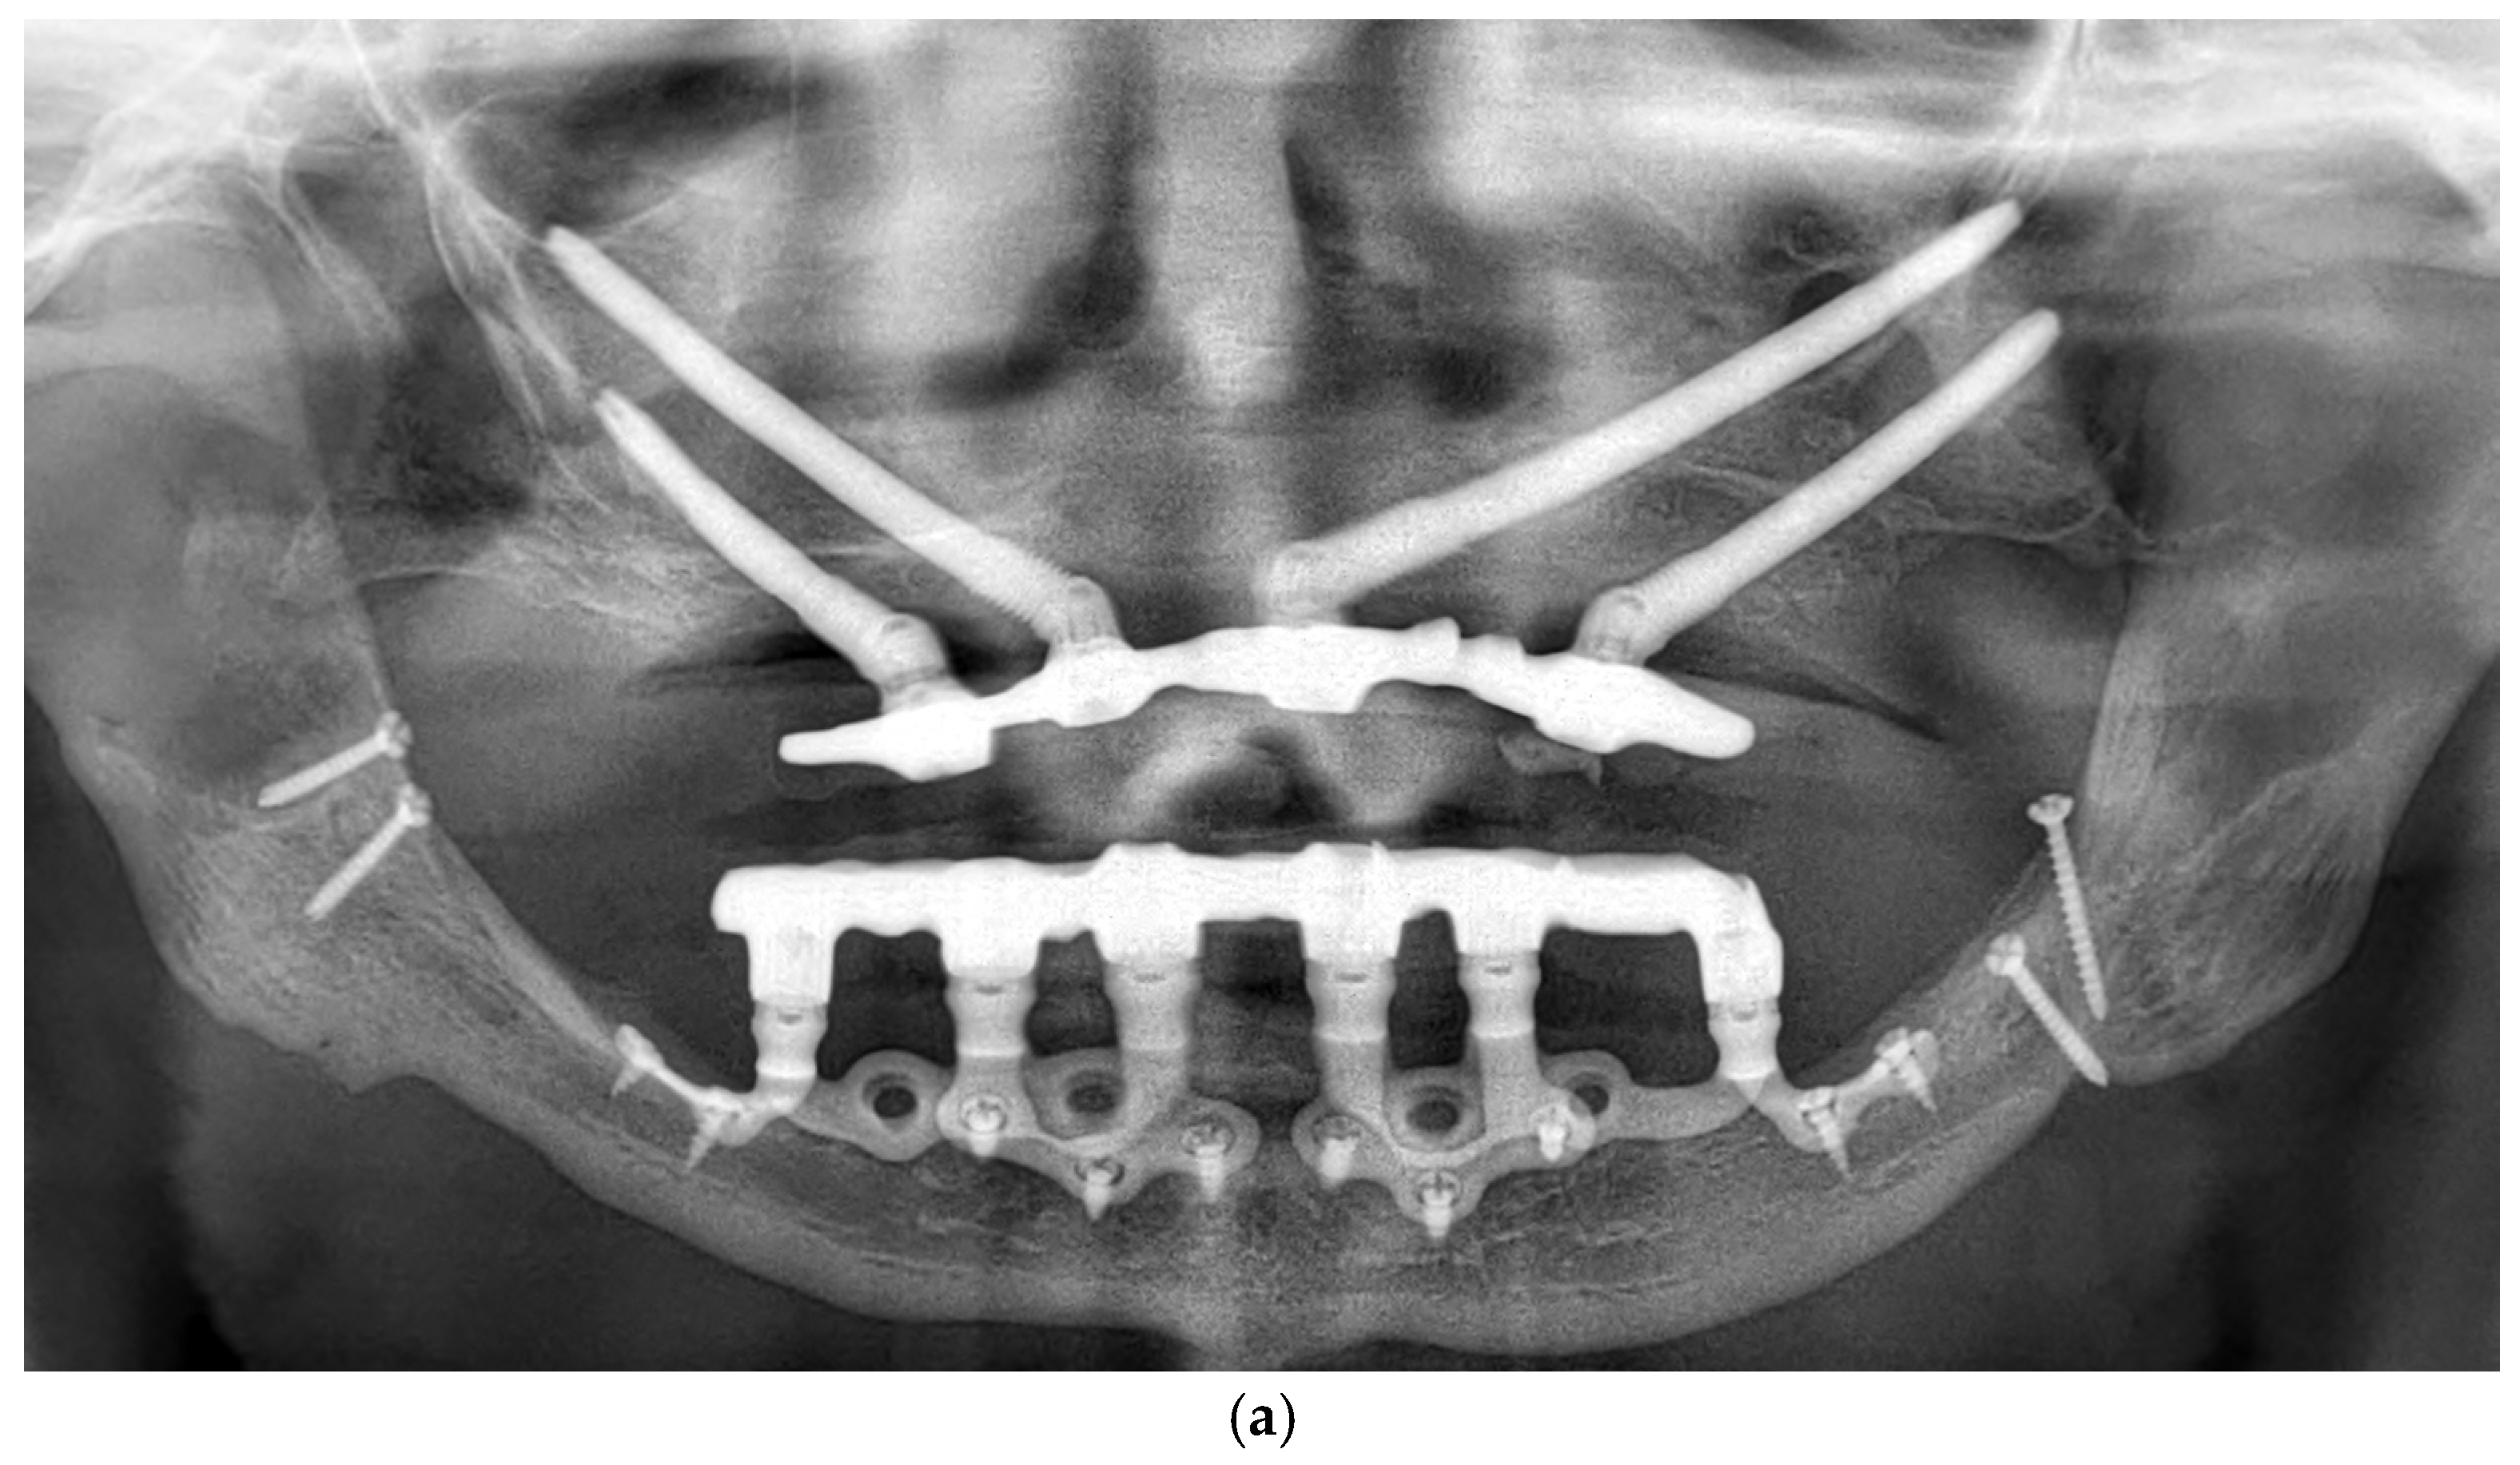

3.11. Case Series

3.11.1. Patient Demographics and Clinical Characteristics

3.11.2. Surgical and Prosthetic Protocol

3.11.3. Complications and Management

- Patient 1: Developed a localized abscess in the region of tooth 13 three months postoperatively, accompanied by soft tissue dehiscence at sites 13, 15, and 17. These were managed with local irrigation and hygiene reinforcement, with full recovery.

- Patient 2: Presented with tissue dehiscence on the lingual side.

- Patient 3: Presented with tissue dehiscence around the second abutment of the upper left implant. The condition was resolved through improved oral hygiene.